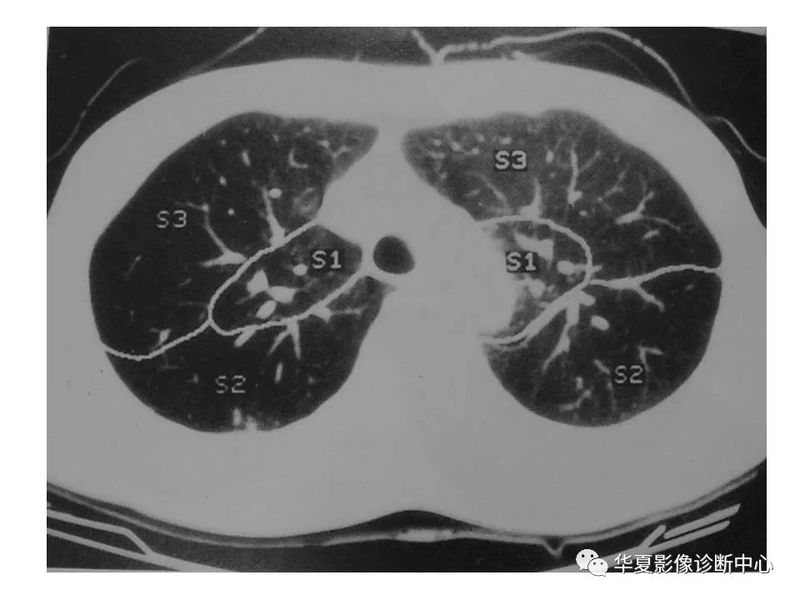

干货 | 汇总胸部CT读片扫盲知识,看懂胸部CT不再难